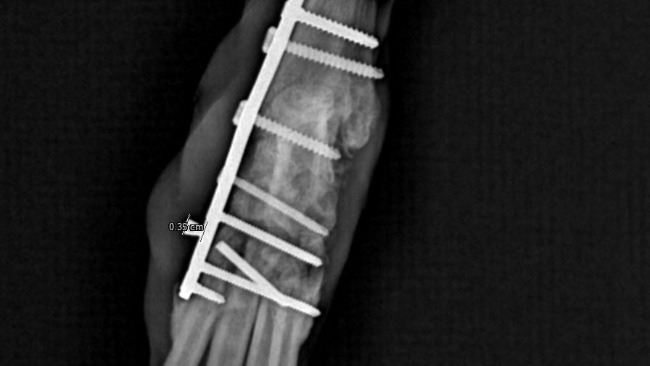

Niedawno Zenek przeszedl ciezka operacje artrodezy ,ratujaca jego łapke .Koszt operacji wyniosl 10tys,dzieki temu ma szanse ocalic lapke i zyc bez bolu .

Niestety Zenek nadal potrzebuje wsparcia ,puscila jedna ze srub ,znowu operacja i dalsze koszty .Prosze pomozcie